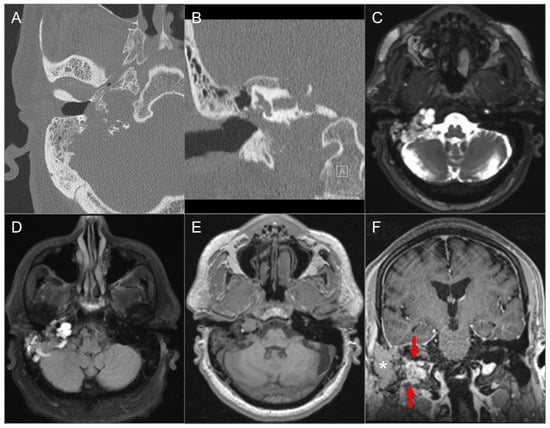

4.4.4. Endolymphatic Sac Tumor